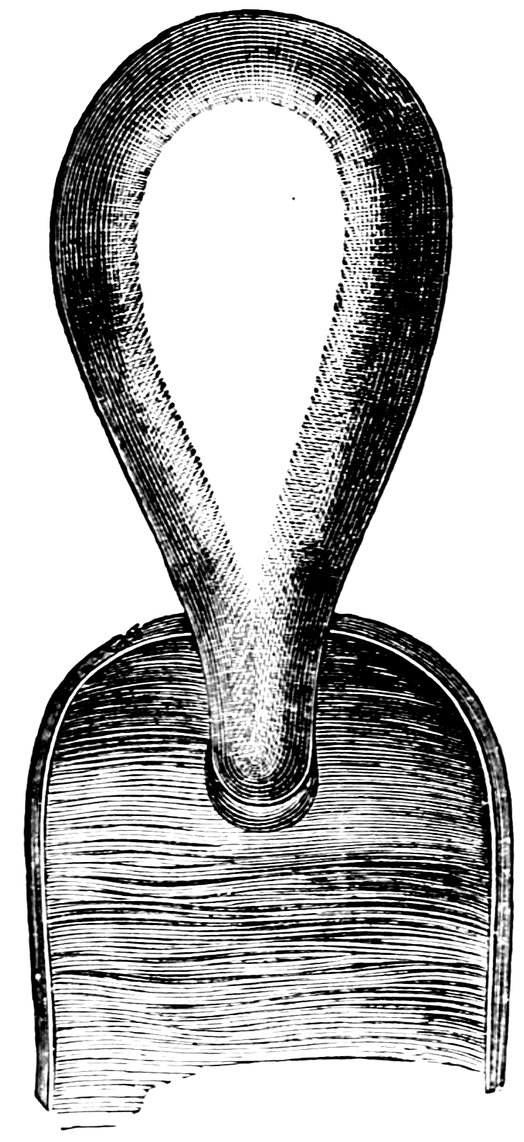

| 42. | Deflorated Septate Hymen | 71 |